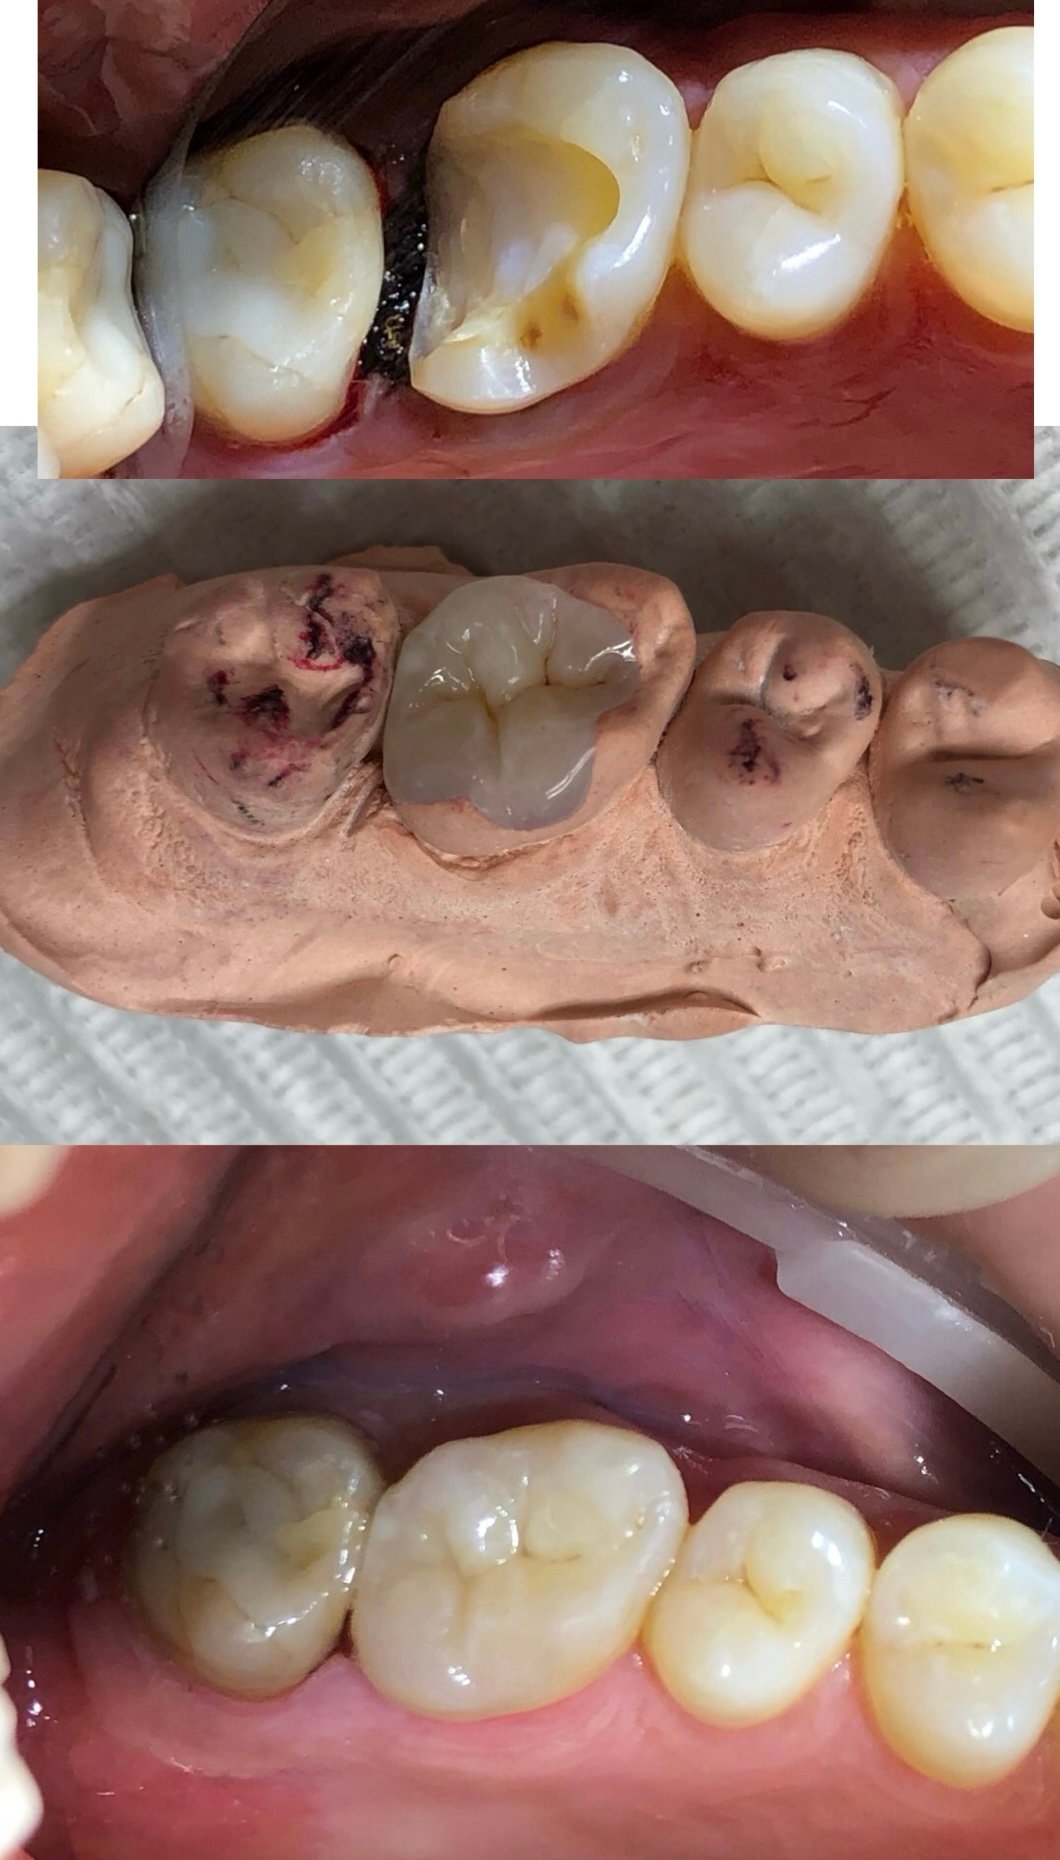

A Dentística Restauradora é uma especialidade da odontologia direcionada na recuperação de dentes danificados, seja por cárie...

Trabalhar dentro da boca do paciente exige muita habilidade, treinamento e conhecimento por parte do dentista...

É um tratamento restaurador que tem por finalidade recuperar o tamanho/altura dos dentes que sofreram desgaste ao longo dos anos...